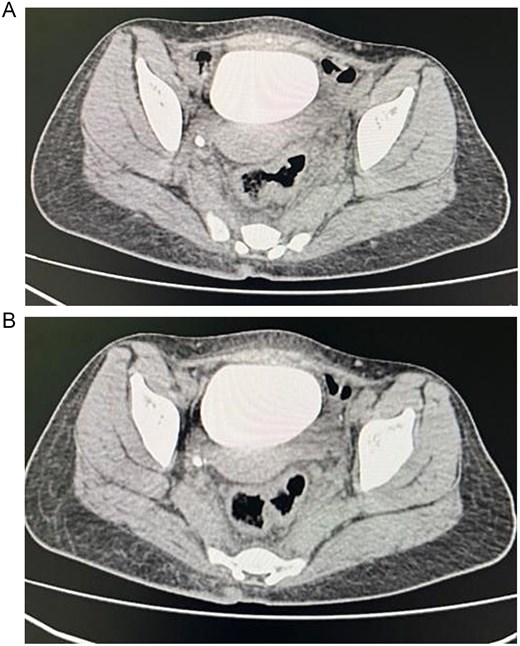

A sigmoidectomy was done, followed by an end to side colorectal anastomosis, with no intraoperative complications. The patient showed significant improvement in her symptoms after surgery by resolving her abdominal pain and urinary symptoms. Follow-up CT cystogram was done, which was unremarkable with no clear vesicorectal or vesicovaginal fistula (Fig. 4). Histopathology was performed and confirmed the presence of diverticular disease with chronic mucosal changes and fibrous tissue consistent with fistula formation, in addition to, the absence of histological evidence of dysplasia, or malignancy.

Showing axial section of the abdominopelvic CT scan with cystogram showing contrast filled urinary bladder with no clear vesicorectal or vesicovaginal fistula.